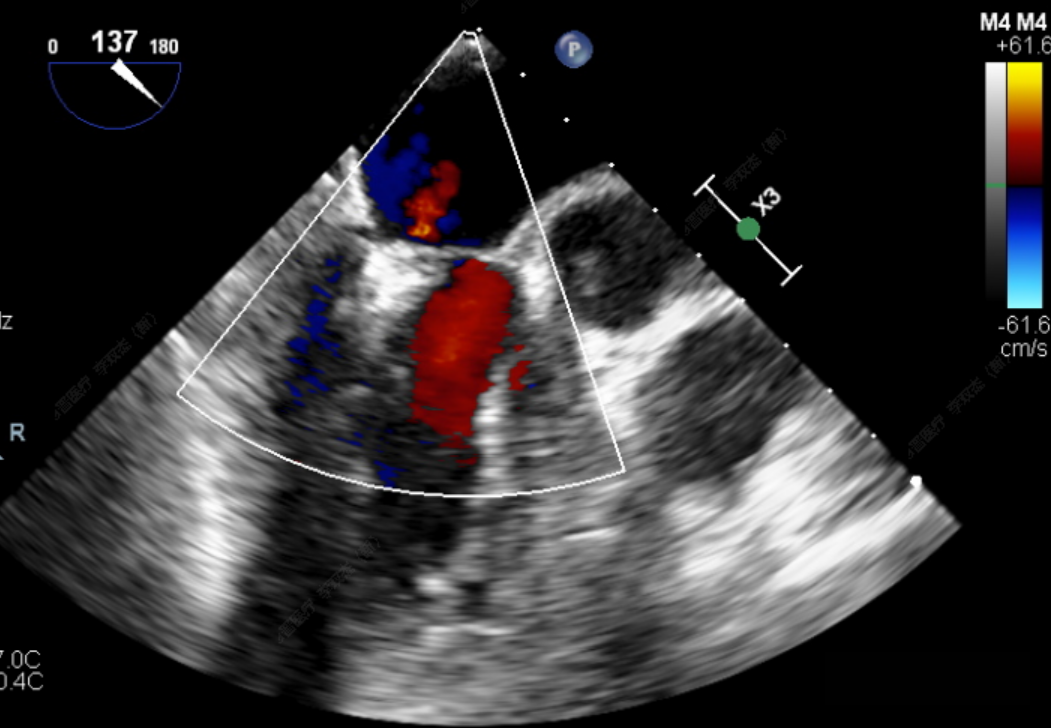

此次手术患者均为高龄、且外科高危的器质性二尖瓣反流,反流病变区域遍及前后瓣叶(一区、二区、三区),复杂及多样性的病变状况大大增加了手术的操作难度性,是对术者与器械稳定及有效性的巨大考验。术中,器械经股静脉穿刺房间隔,通过输送系统送入患者左心房,到达二尖瓣膜反流处,在经食道超声及DSA引导下,通过反复评估脱垂范围、抓捕位置、反流程度,确保细致操作、精准夹合、释放。术后即刻,患者反流显著减小,左房压下降,血流动力学改善明显,短暂过渡后,首位患者安返病房。导管室内,华西心脏瓣膜团队仍严阵以待,为之后两例手术做准备,经过团队之间紧密配合,三台手术均顺利完成。